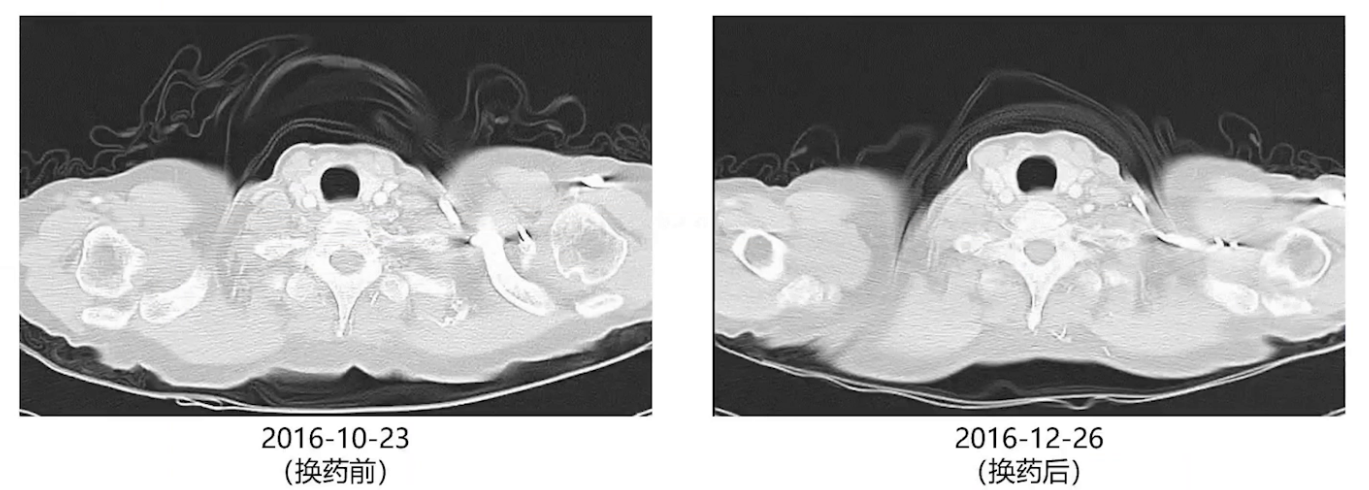

术后3个月、6个月及9个月复查,双肺结节逐渐增大,考虑厄洛替尼耐药,2016年10月改服奥西替尼。两个月后影像复查,双肺增大的结节再次缓解。此后每2-3个月复查胸部增强CT,每半年进行一次全身检查。